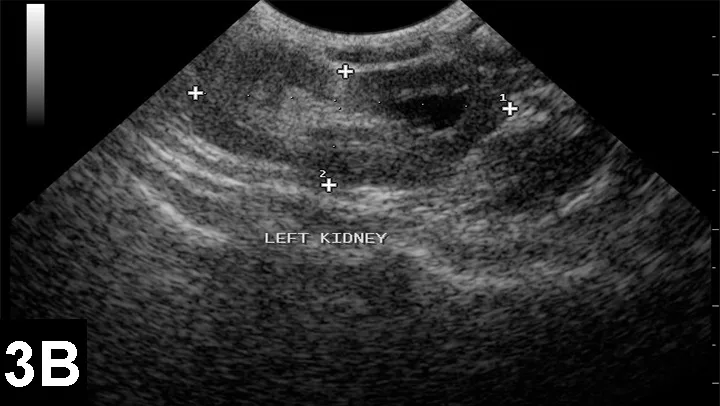

UltrasonographyUltrasonography may be used to diagnose some gastrointestinal disorders, including ileus, intussusception, and enteritis; abdominal effusion from hemorrhage, peritionitis, or ruptured bladder; some congenital renal diseases (Figure 3); and pneumothorax and some heart defects.